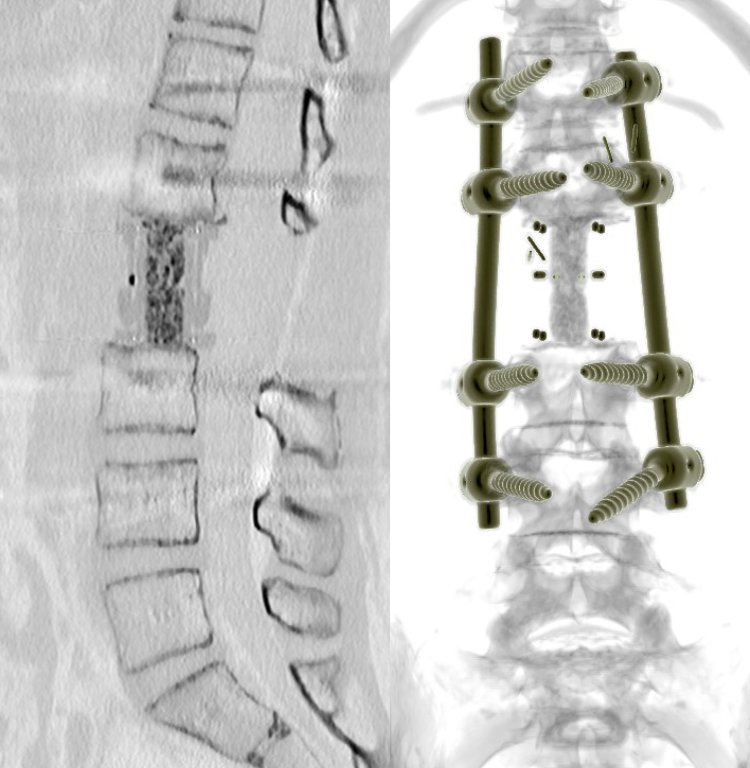

Gerincdaganat en bloc rezekció utáni CT rekonstrukció — sagittális és AP nézet instrumentációval

Rezecție tumorală en bloc și reconstrucție: CT sagital cu înlocuirea corpului vertebral (stânga) și reconstrucție 3D cu instrumentație posterioară (dreapta)